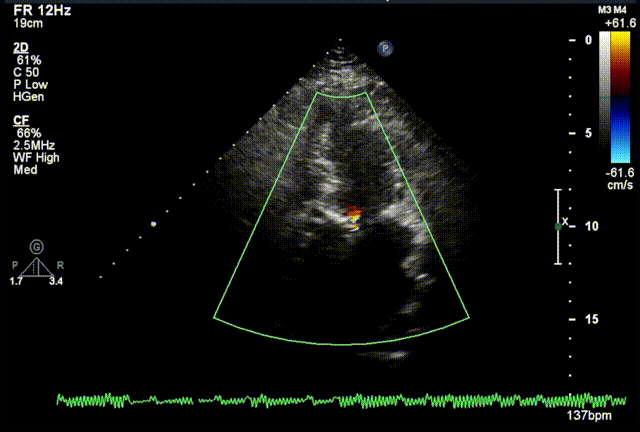

术后超声